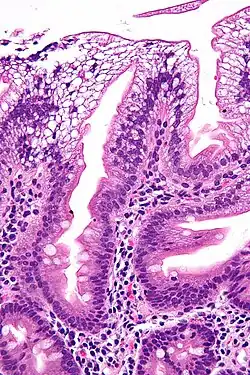

Micrograph showing enterocytes with a clear cytoplasm (due to lipid accumulation) characteristic of abetalipoproteinemia. Duodenal biopsy. H&E stain. | |

There is an absence of apolipoprotein B. On intestinal biopsy, vacuoles containing lipids are seen in enterocytes. This disorder may also result in fat accumulation in the liver (hepatic steatosis). Because the epithelial cells of the bowel lack the ability to place fats into chylomicrons, lipids accumulate at the surface of the cell, crowding the functions that are necessary for proper absorption.